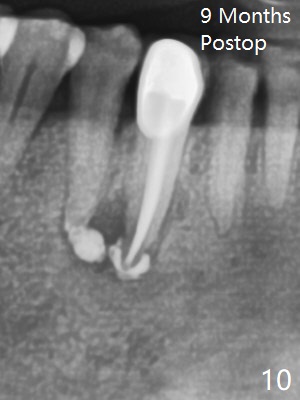

The patient reports that the fistula disappears after initial RCT at #27, but it seems to re-appear 1 month post canal debridement (Fig.5 >). After repeated debridement with #40 hand file at 23 mm, apply Endo Sequence BioCeramic Sealer and insert GT 40/.08 master cone with black carrier (Fig.6). One hour later, the patient returns with re-appearance of the fistula (Fig.7). Following local anesthesia, poking the fistula leads to sealer escape (Fig.8). After debridement of the fistula until the bone, PA is retaken (Fig.9). A crown was made in China; mesial radiolucency starts (Fig.10). The tooth remains asymptomatic 1 year 5 months postop (Fig.11). There is a lingual fistula with enlarged mesial radiolucency 2 years 3 months postop (Fig.12-14).